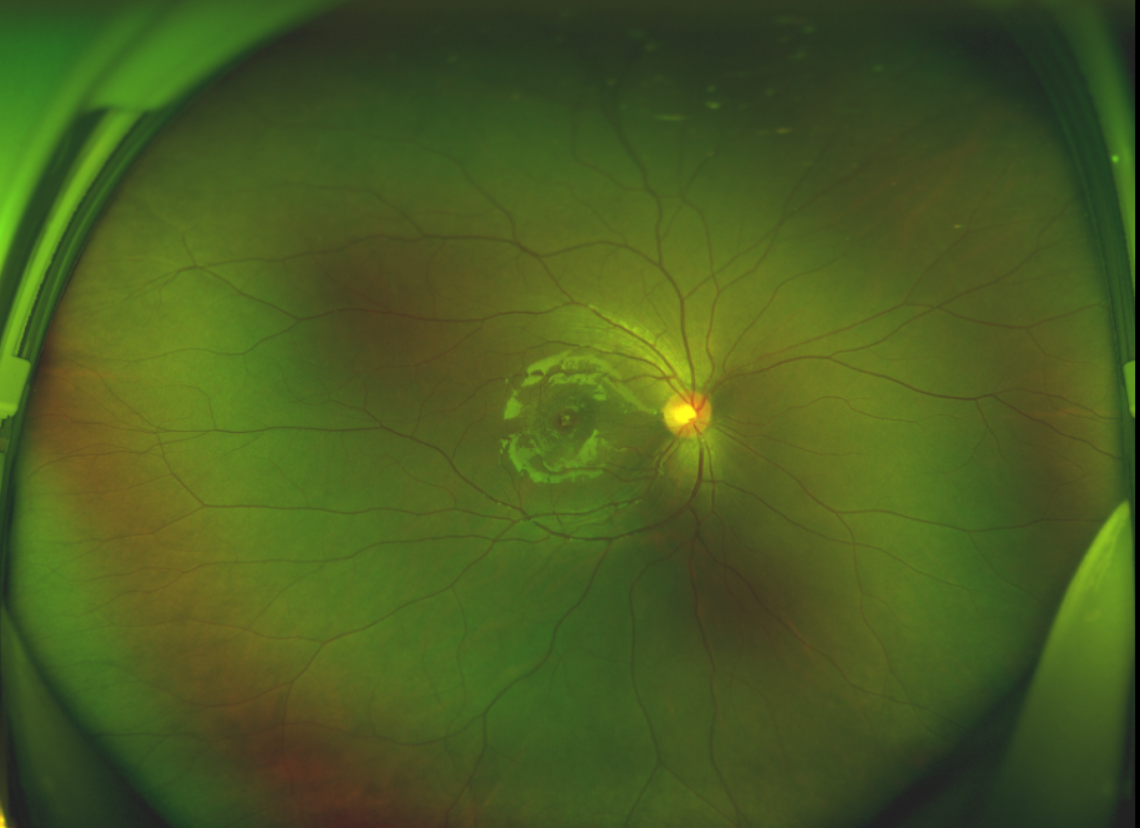

半年前的一次意外,誠誠(化名)右眼不慎受傷導(dǎo)致黃斑裂孔。從此,他的“視”界不再清晰,也不再有直線條……

黃斑位于視網(wǎng)膜正中心,是視覺最敏銳的區(qū)域,堪稱“眼底的心臟”,負(fù)責(zé)我們閱讀、駕駛、識(shí)別人臉等精細(xì)視覺。 當(dāng)黃斑區(qū)的神經(jīng)組織出現(xiàn)全層缺損,形成一個(gè)“孔洞”,即為黃斑裂孔,它會(huì)直接導(dǎo)致中心視力急劇下降、視物變形、視野中心出現(xiàn)暗區(qū)。

由于裂孔較小,當(dāng)?shù)蒯t(yī)院建議先觀察,看看裂孔是否能夠自愈。可半年時(shí)間過去了,誠誠傷眼的裂孔不僅沒有愈合的跡象,反而越來越大,這讓家長的心揪得更緊了。

經(jīng)過詳細(xì)的檢查和評(píng)估,王曉波主任決定采用“內(nèi)界膜翻轉(zhuǎn)覆蓋聯(lián)合粘彈劑固定術(shù)”為誠誠進(jìn)行治療。

除此之外,利用自體組織覆蓋為黃斑裂孔提供了理想的愈合環(huán)境,裂孔閉合速度顯著快于傳統(tǒng)方法。誠誠接受手術(shù)24小時(shí)后,檢查可見內(nèi)界膜瓣位置良好;術(shù)后1個(gè)月,黃斑裂孔已經(jīng)閉合,視力恢復(fù)到0.5;術(shù)后兩個(gè)月,視力進(jìn)一步提升到0.7。